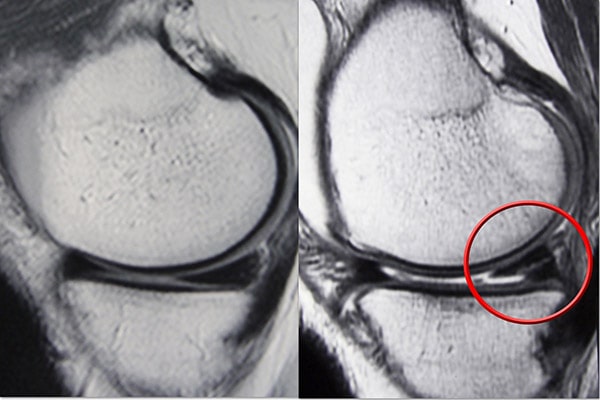

磁共振成像 (MRI) 掃描。 MRI 掃描可評(píng)估膝關(guān)節(jié)的軟組織,包括半月板、軟骨、肌腱和韌帶。

半月板可能因急性創(chuàng)傷或隨著時(shí)間的推移發(fā)生退行性變化而撕裂。眼淚通過(guò)它們的外觀以及半月板發(fā)生撕裂的位置來(lái)記錄。常見(jiàn)的撕裂包括桶柄、襟翼和徑向。

半月板外側(cè)三分之一的血供豐富。這個(gè)“紅色”區(qū)域的撕裂可能會(huì)自行愈合,或者通常可以通過(guò)手術(shù)修復(fù)。縱向撕裂是這種撕裂的一個(gè)例子。

相比之下,半月板內(nèi)部三分之二的血液供應(yīng)不足。沒(méi)有血液的養(yǎng)分,這個(gè)血流受限的“白色”區(qū)域的眼淚就無(wú)法愈合。由于碎片不能重新長(zhǎng)在一起,因此通常通過(guò)手術(shù)修剪該區(qū)域?qū)ΡJ刂委煙o(wú)反應(yīng)的癥狀性撕裂。